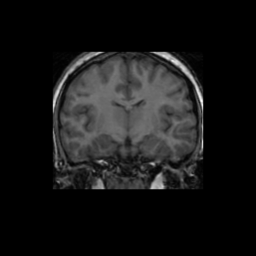

Test/Retest Reliability

FSL was run on each scan in the Brain Segmentation Testing Protocol (BSTP) between-scanner test/retest dataset. Select a subject below to see volumes for each subject across the subject's scans.